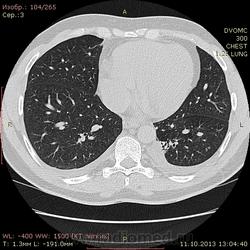

Пациент 35 лет. На УЗИ нашли житкость слева в плевральной полости, отправили на КТ - жидкость с обеих сторон. Из разговора с больным выяснилось, что около 1,5 месяцев назад была высокая тенпература, кашель - никуда не обращался и не лечился. На момент исследования ни на что не жалуется.

Похоже слева в S10? на поствоспалительные изменения? или на что похуже? И если на стороне поражения можно понять окуда жидкость, то справа - можно расценивать как реакция плевры на воспаление слева?

Локальный фиброз субсегмента S10 слева с бронхоэктазами. Двусторонний малый гидроторакс (толщина слоя жидкости до 1 см≈объём до 50 мл). Интересная субкапсульная ерундовина в S6 печени, наверное киста.